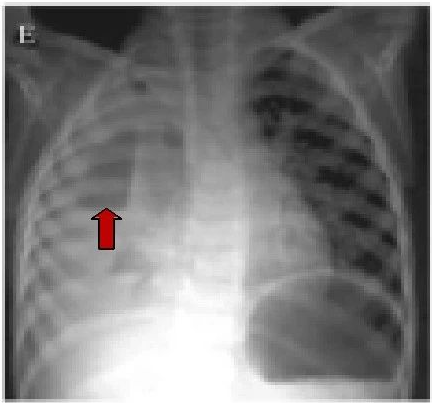

单纯性小肠梗阻(中腹部见多个阶梯状气液平面及胀气肠襻.

03 气液平征 气液平表明存在肺脓肿或带有支气管胸膜瘘的脓胸.

扩张,积气积液,立位片可见高低不 平的气液平面呈不连续的阶梯状排列

气液平面x线图片

气液平面